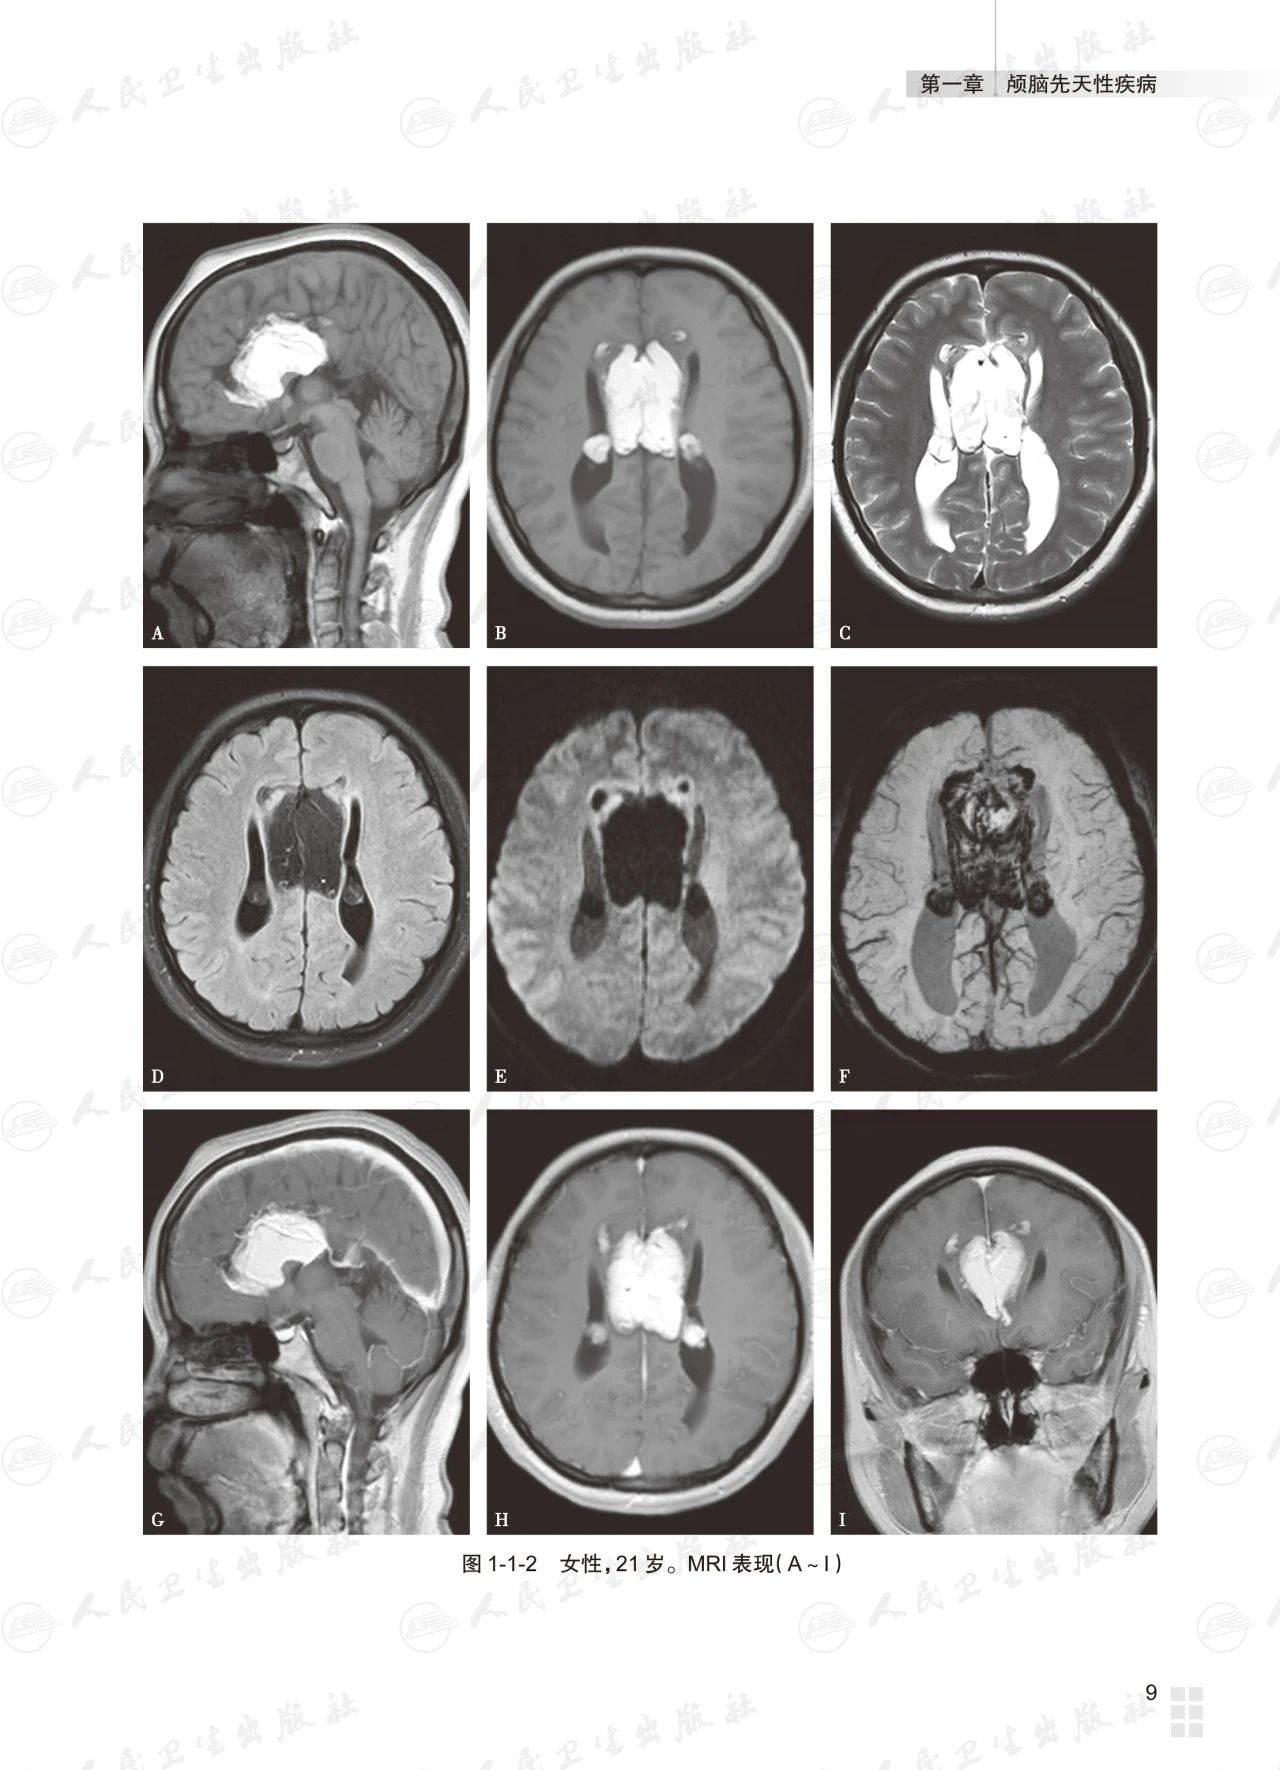

基础篇为常见颅脑疾病多模态磁共振成像典型病例分析,以复习为主,从疾病的临床与病理入手,解析影像学特征,提供影像诊断思路,最终给出诊断要点;